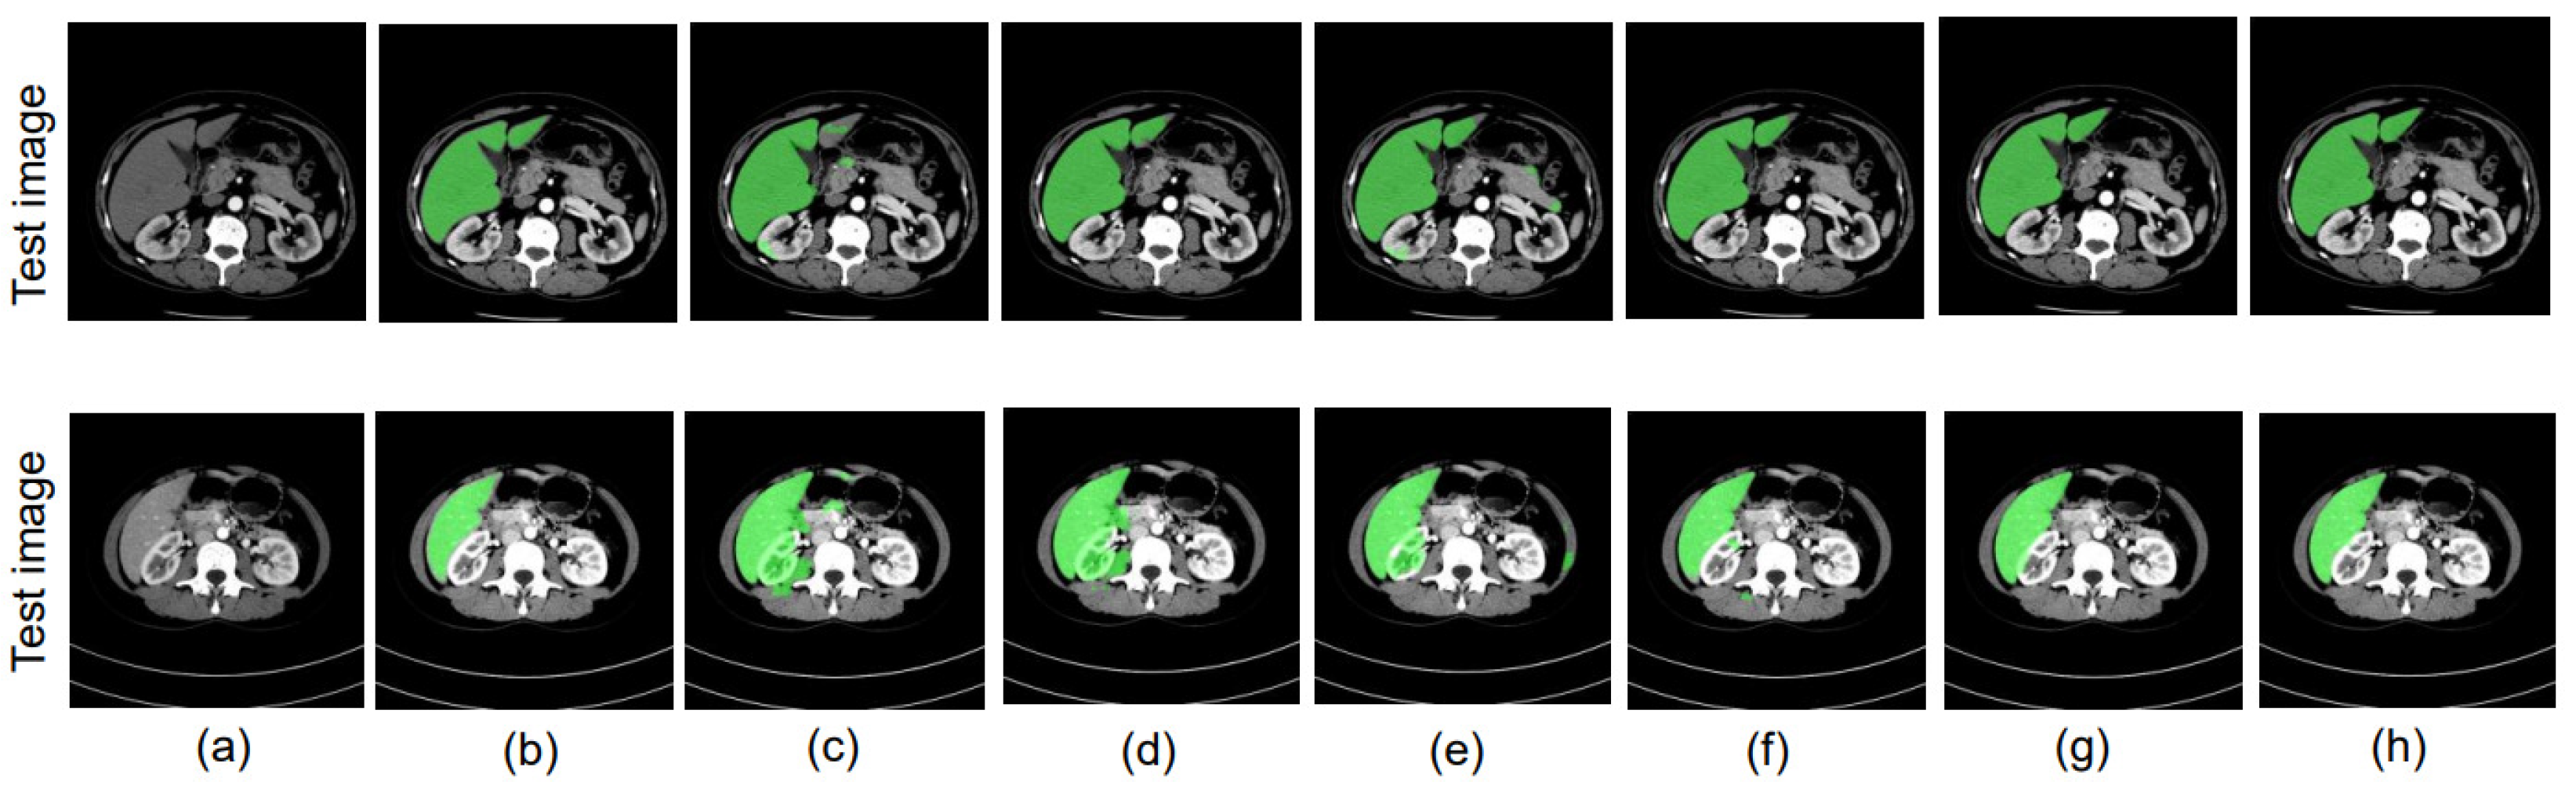

4.8. Ablation Study

4.8.1. Different Datacenter and Same Phase

4.8.2. Same Datacenter and Different Phase

4.8.3. Different Datacenter and Different Phase

4.9. Evaluation of Proposed Methods with SegNet as the Backbone